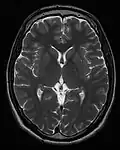

Exemplos de exames de ressonância magnética ponderada T1, ponderada em T2 e ponderada por DP.

Cada tecido retorna ao seu estado de equilíbrio após a excitação pelos processos independentes de T1 (spin-tretice) e T2 (spin-spin) de relaxamento. Para criar uma imagem ponderada em T1, a magnetização pode ser recuperada antes de medir o sinal MR, alterando o tempo de repetição (TR). Esta ponderação de imagem é útil para avaliar o córtex cerebral, identificando tecido adiposo, caracterizando lesões focais e, em geral, para obter informações morfológicas, bem como para imagens pós-contraste. Para criar uma imagem ponderada em T2, a magnetização pode decair antes de medir o sinal MR alterando o tempo de eco (TE). Esta ponderação de imagem é útil para detectar edema e inflamação, revelando lesões de substância branca e avaliando a anatomia zonal na próstata e no útero.